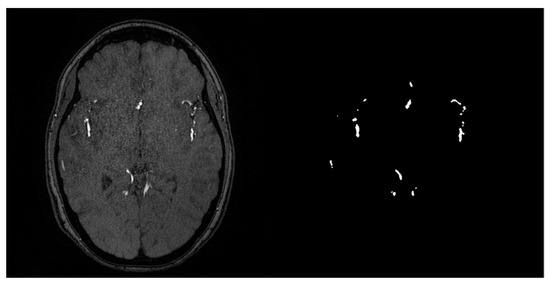

- A.

- MRA Images